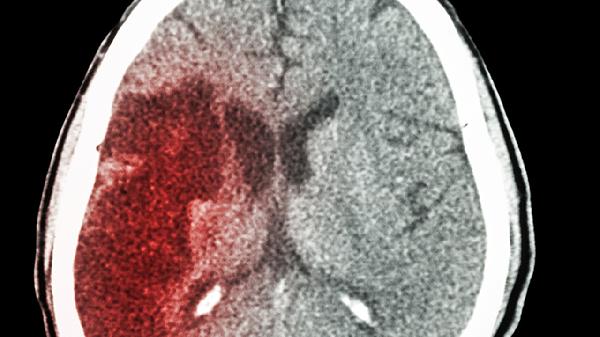

26岁小伙突发脑梗,医生警告:这3个习惯比熬夜更危险!

26岁就脑梗?这个数字让很多年轻人倒吸一口凉气。别以为脑梗是老年病,医院急诊科的数据显示,30岁以下脑梗患者比例五年间增长了200%。更令人意外的是,诱发脑梗的元凶可能就藏在你的日常习惯里。